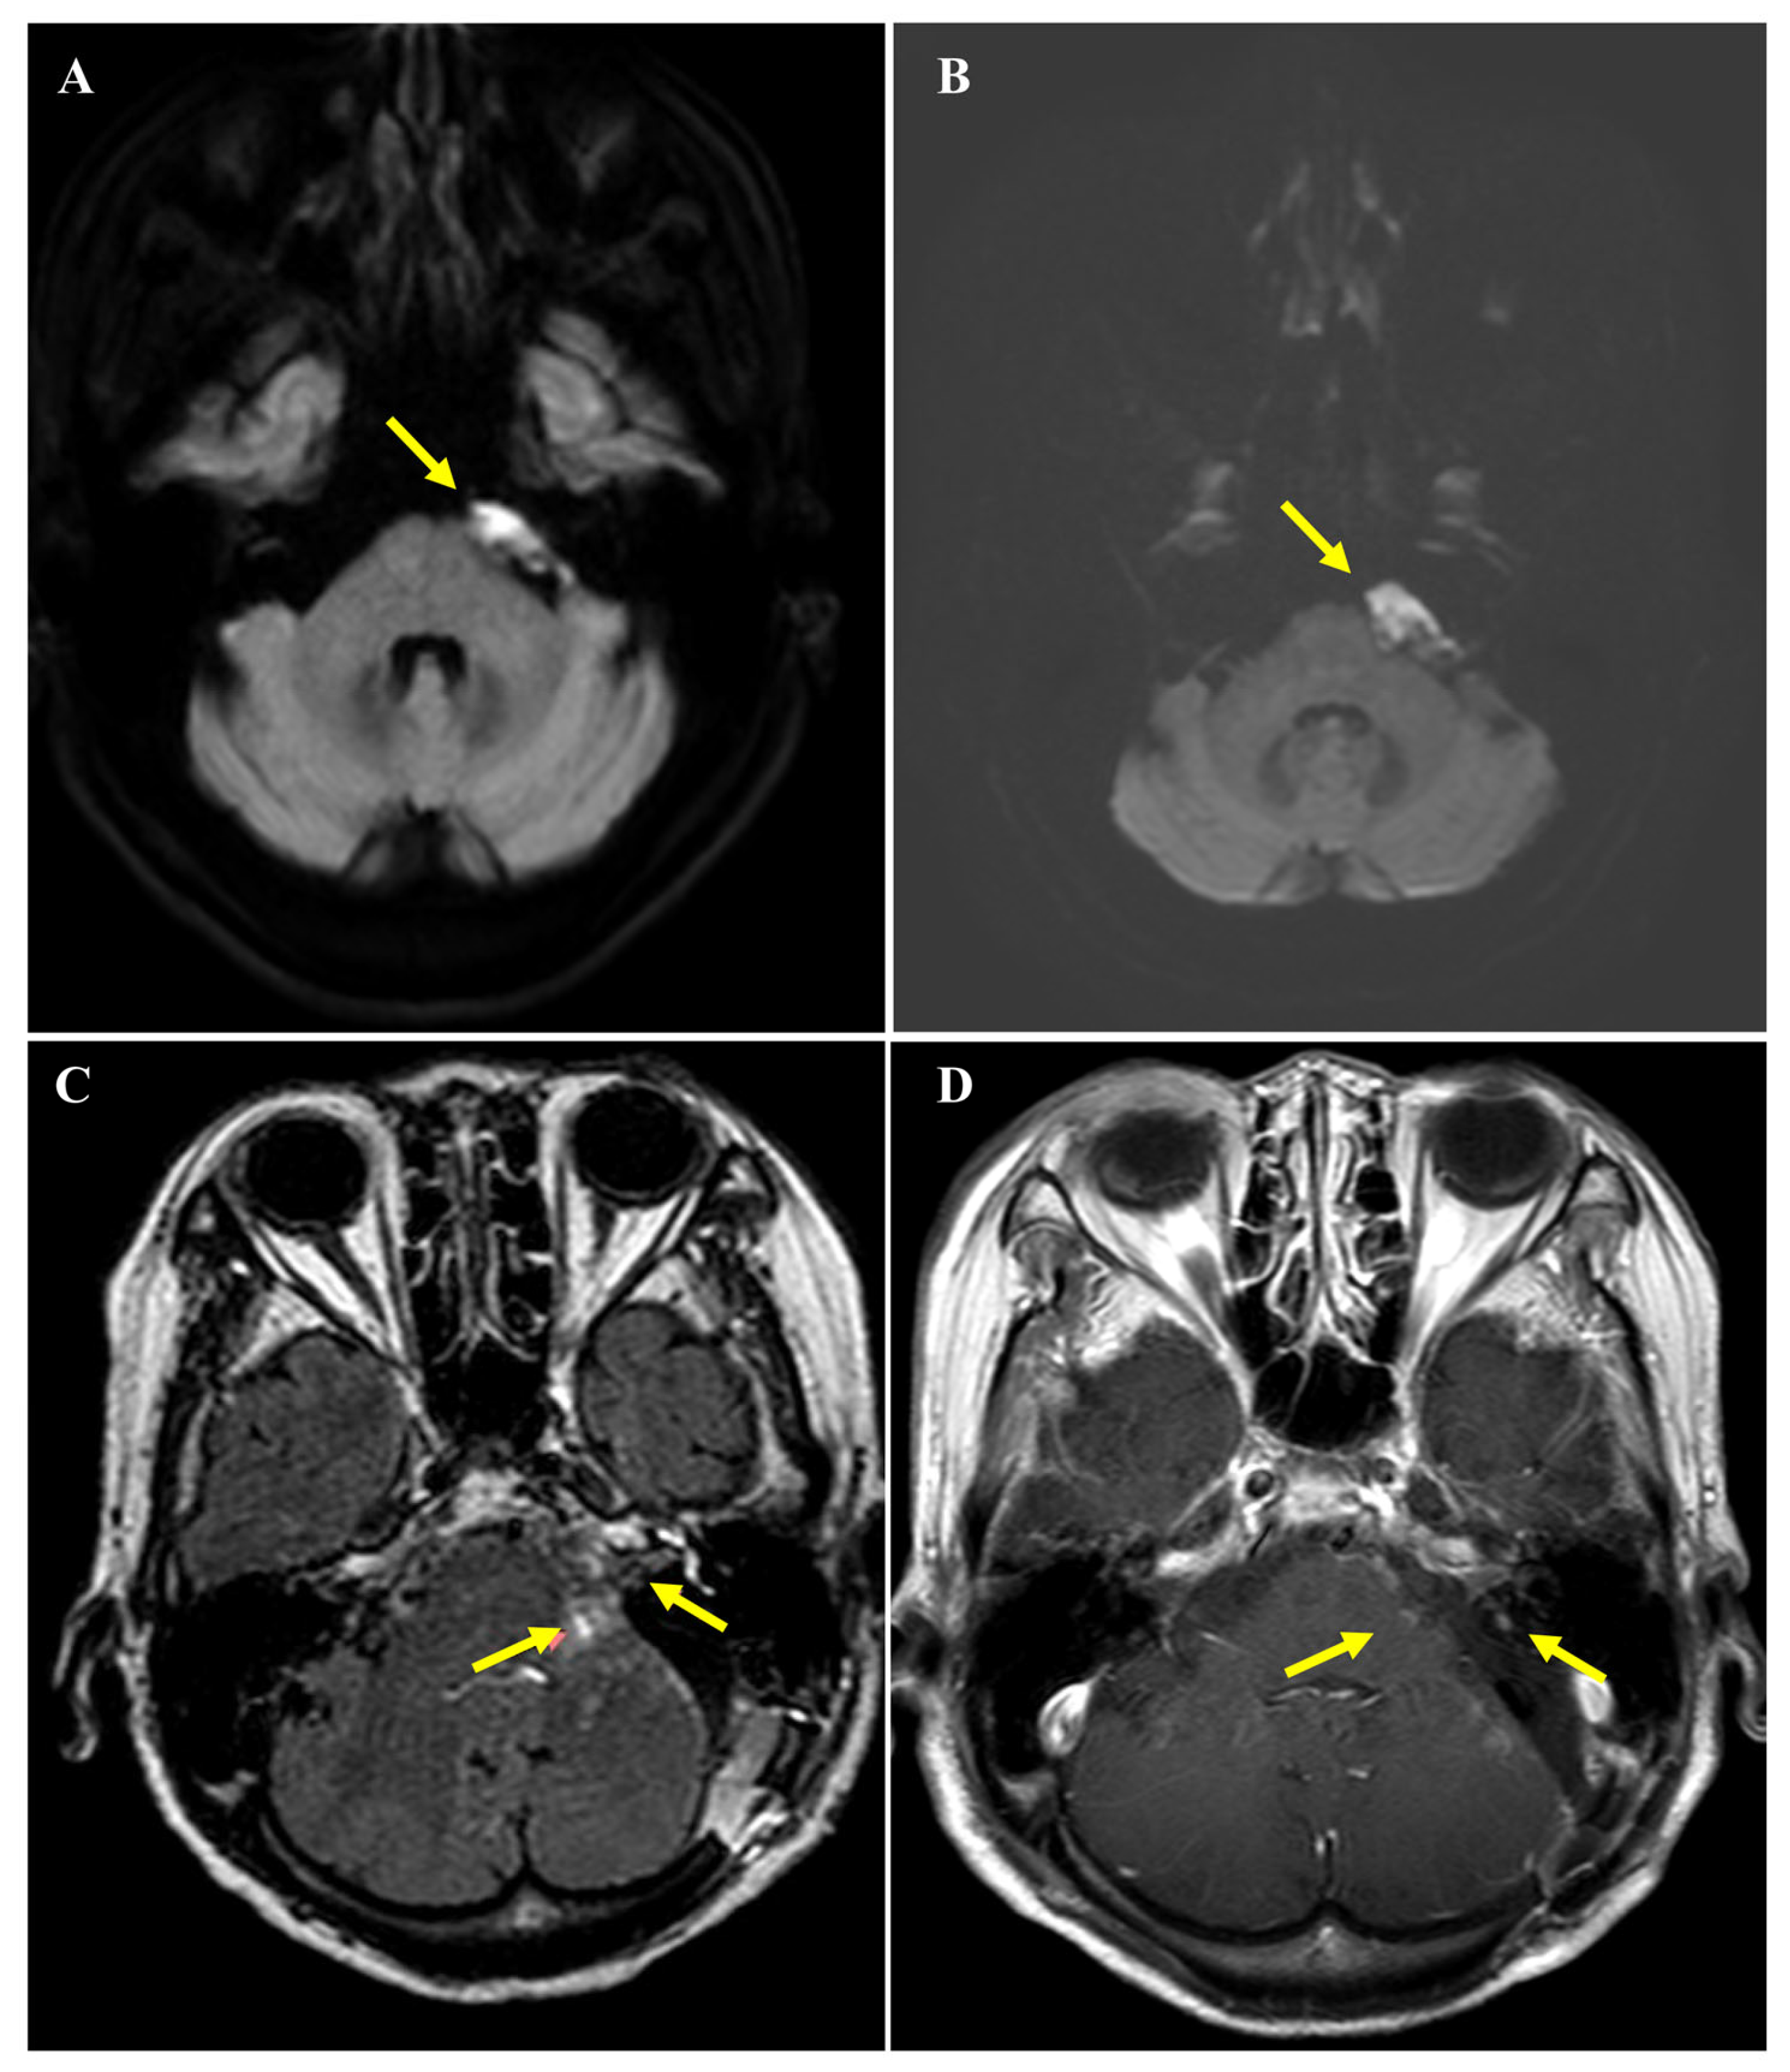

Routine surveillance brain magnetic resonance imaging (MRI) performed three years prior to the current presentation had identified a 2.3 × 1.1 cm non-enhancing lesion in the left CPA. The lesion demonstrated restricted diffusion characteristic of an intracranial epidermoid cyst and had shown no interval change compared to imaging studies from the preceding decade (Figure 1A). However, approximately two weeks before presentation, the patient experienced a sudden exacerbation of dizziness that severely compromised her ability to ambulate independently. An urgent MRI showed no significant mass effect or hydrocephalus, and her symptoms transiently responded to conservative medical management. Unfortunately, this improvement was short-lived; within days, she developed persistent, high-pitched tinnitus and subjective profound hearing loss on the left side. A follow-up diffusion-weighted MRI revealed equivocal morphological changes with a subtle enlargement of the lesion to 2.6 × 1.1 cm (Figure 1B). Although the size increase was minimal, the acute onset of cochleovestibular symptoms raised concern for clinically significant disease progression, ultimately leading to a decision to proceed with surgical intervention.

Figure 1.

Serial magnetic resonance imaging (MRI) findings before surgery and prior to Gamma Knife radiosurgery. (A) Axial diffusion-weighted MRI demonstrating a well-defined lesion at the left cerebellopontine angle (arrow) with imaging features consistent with an intracranial epidermoid cyst, measuring approximately 2.3 × 1.1 cm, without significant mass effect on adjacent brainstem structures. (B) Follow-up axial diffusion-weighted MRI showing equivocal interval change with subtle enlargement of the left cerebellopontine angle lesion (arrow) to approximately 2.6 × 1.1 cm, while no definite mass effect or hydrocephalus is observed. (C) Axial post-contrast T2 fluid-attenuated inversion recovery MRI obtained on postoperative brain MRI before Gamma Knife radiosurgery demonstrating residual enhancing tumor components at the left cerebellopontine angle and extension into the internal auditory canal (arrows) following subtotal resection. Mild residual mass effect on the left pons and slight displacement of the ipsilateral facial and vestibulocochlear nerve complex are also noted. (D) Axial contrast-enhanced T1-weighted spin-echo MRI obtained 18 months after Gamma Knife radiosurgery demonstrating marked reduction of the residual tumor at the left cerebellopontine angle and decreased extent of enhancing lesions within the left internal auditory canal (arrows), consistent with radiographic response and no evidence of disease progression.

Postoperatively, the patient’s case was reviewed by a multidisciplinary tumor board. While definitive EBRT or IMRT could be considered as a viable option of care for malignant CPA tumors, these options were deemed suboptimal for this patient. Her advanced age, limited functional reserve, and history of cerebrovascular disease raised concerns regarding her ability to tolerate a prolonged 6-week course of wide-field radiation. Furthermore, the residual tumor’s proximity to the brainstem posed a high risk of radiation-induced toxicity. Consequently, GKS was selected as a focused, hypofractionated salvage modality. Pre-radiosurgical MRI visualized residual enhancing nodules in the CPA and IAC (Figure 1C). SRS was delivered to these two target volumes (352 mm3 and 219 mm3) with a marginal dose of 18 Gy at the 60% isodose line (maximum dose: 30 Gy). The procedure was completed without acute complications. At 18 months post-radiosurgery, serial follow-up MRIs have demonstrated stable disease with no evidence of local recurrence or distant metastasis (Figure 1D), and the patient remains neurologically stable at her baseline.